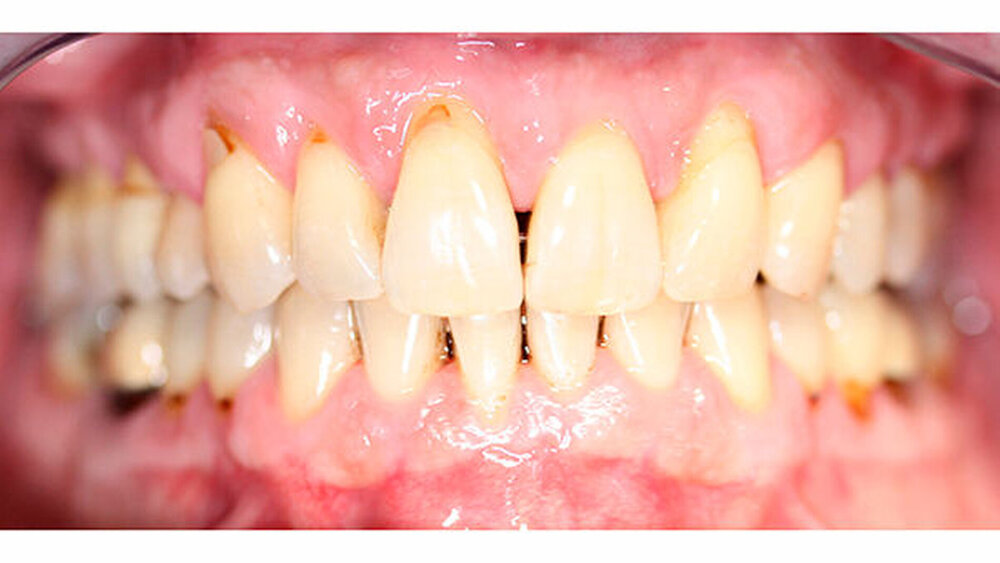

Nach erfolgter Parodontitistherapie und konservierender Versorgung stellte sich der Patient Ende 2014 erneut in unserer Praxis vor.

Die Sulkustiefen konnten auf etwas weniger als 4 mm reduziert werden, während der Blutungs- und Plaque-Index bei weniger als 15 Prozent lag. Daher wurde eine kieferorthopädische Behandlung über die nächsten zwei Jahre in Kombination mit engen zahnärztlichen Kontrollen geplant. Als Mittel der Wahl entschieden wir uns gemeinsam mit dem Patienten für das Invisalign-System, da hiermit sowohl eine Schienung als auch eine kraft-arme Bewegung der Zähne möglich sein sollte. Für den Frontzahnbereich wurden keine Attachments geplant, so dass hier eine unnötige Hebelwirkung umgangen werden konnte (Abbildung 3).